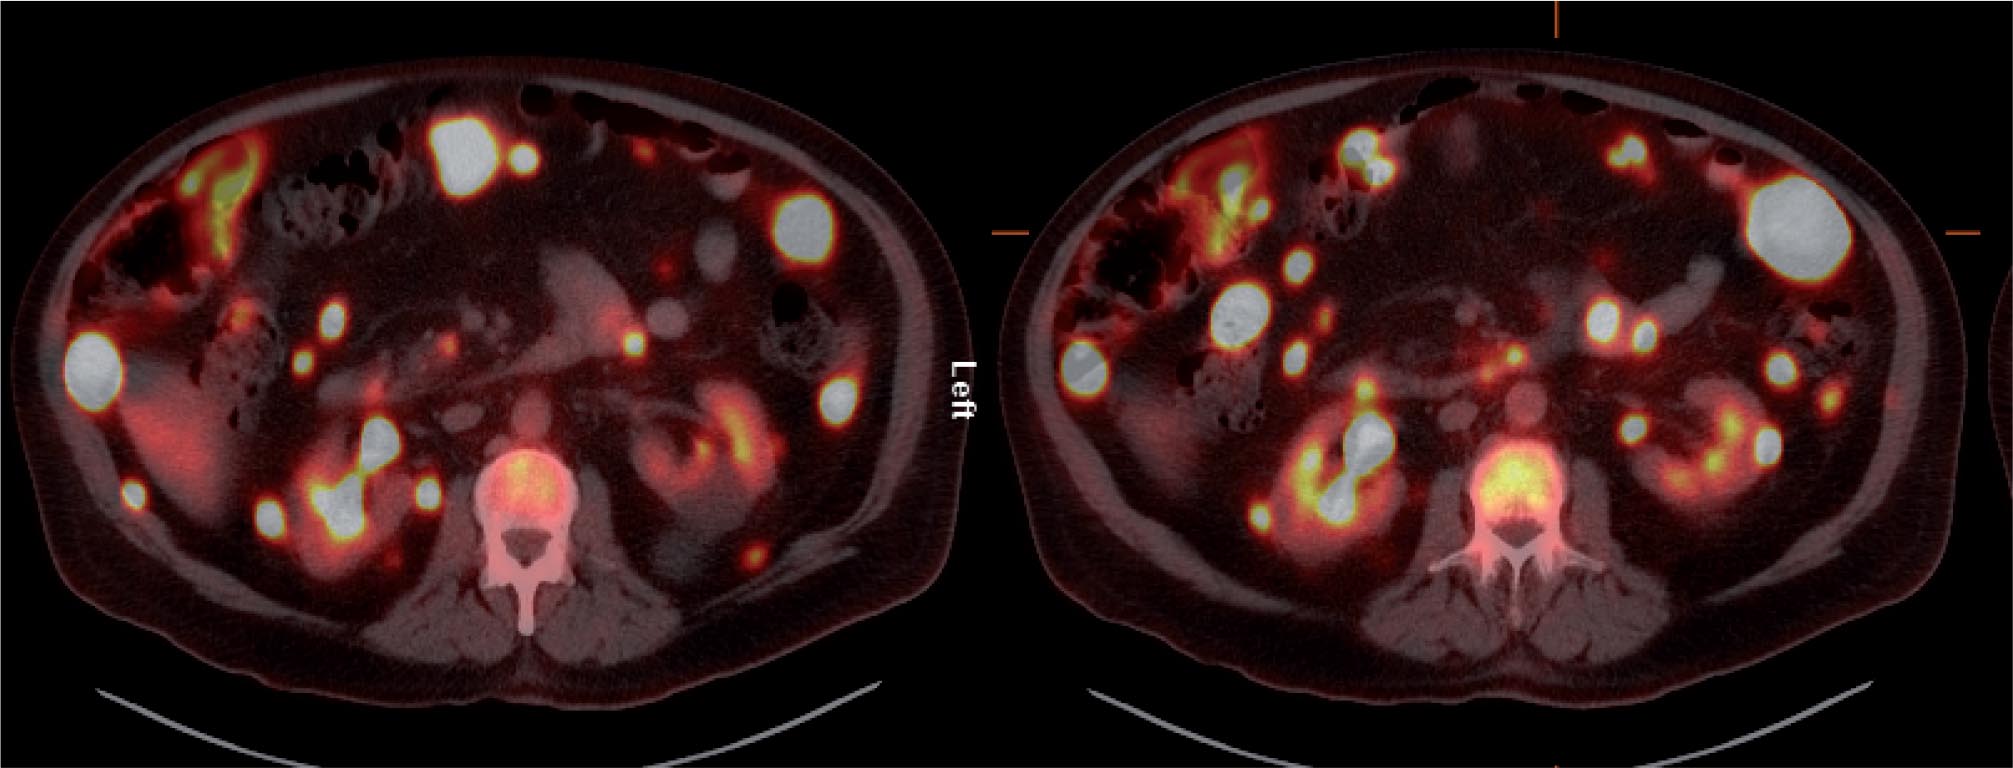

The patient was referred for 18F-FDG-PET/CT the next day to further evaluate the disease extent. A whole-body PET/CT was performed 60 min after the intravenous injection of 629 MBq (17 mCi) 18F-FDG. The study showed multiple hypermetabolic foci throughout the body (Figure 1). There was a large soft tissue mass in the right lower lobe with increased 18F-FDG uptake; the maximum standardized uptake value (SUVmax) of this lesion was 38.0. Also, there were multiple hypermetabolic nodules in the thyroid, gastric mucosa, pancreas, and both the adrenals. Both kidneys contained exophytic lesions with increased 18F-FDG uptake (Figure 2). A circumferential soft tissue mass in the esophagus was hypermetabolic as well. Additional FDG-avid nodules and masses were also found in the peritoneum and omentum; the largest of these had a SUVmax of 68.0. Intense FDG uptake was observed in multiple subcutaneous and intramuscular nodules throughout the body, some of which were thought to represent lymph nodes. Brain magnetic resonance imaging was performed on the same day, which revealed five metastatic lesions measuring up to 1.5 cm in the left frontal lobe, anterior right parietal lobe, and right temporal lobe. At this point, there were multiple candidate lesions for the primary malignancy, such as lung, esophagus, melanoma, or an aggressive lymphoma.

Fig 2

Figure 2. Axial 18F-FDG PET/CT fusion images. Foci of markedly increased 18F-FDG uptake are shown in the peritoneal cavity, and in exophytic lesions in the kidneys bilaterally.